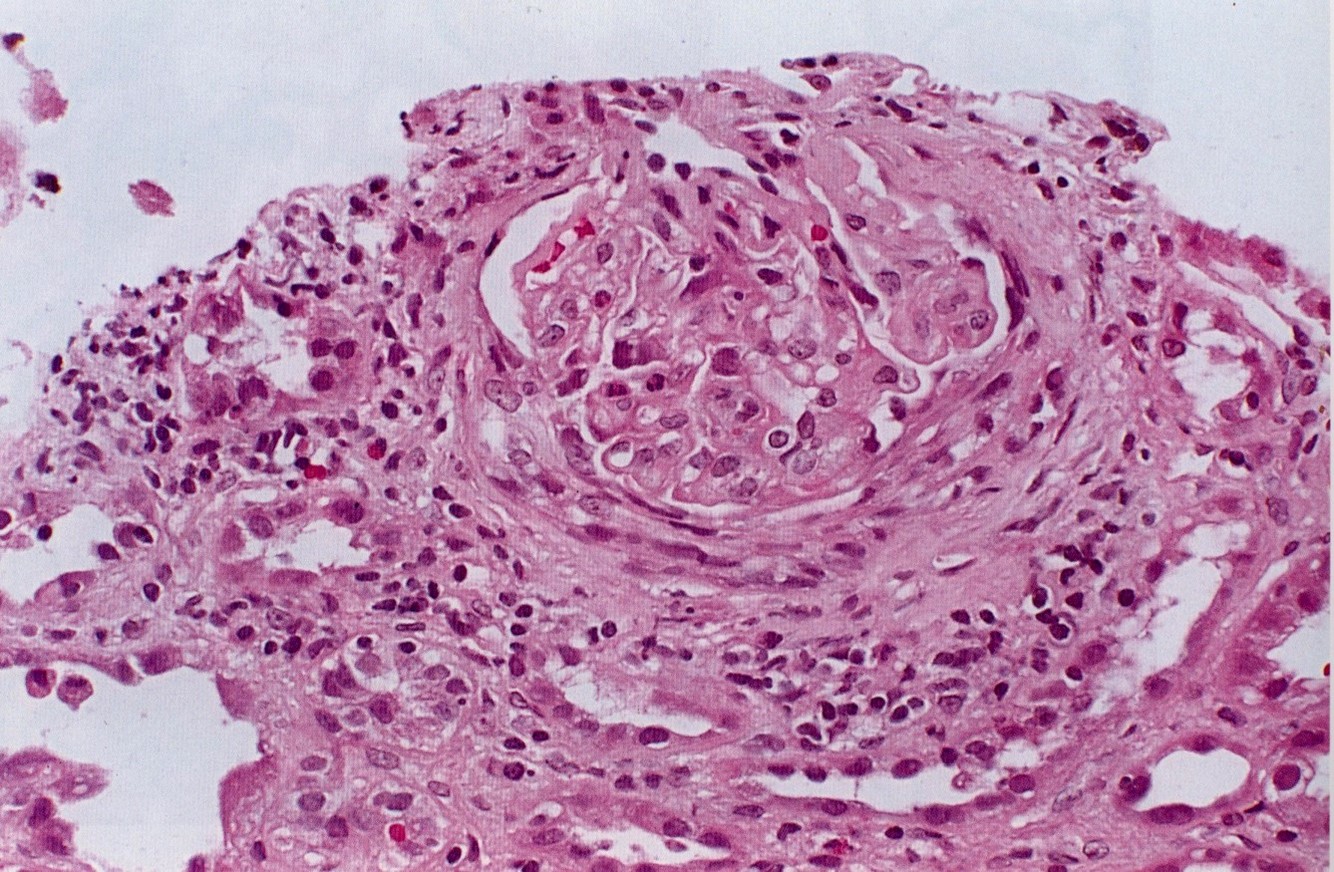

Crescent Formation

Bowmans capsule compressing the tuft. Both kidneys will die within hours. Must get dialysis quickly or pt will die.

Crescent Formation of Acute Post Strep GMN / Rapidly Progressive GMN

Inflammatory cells surround the compressed capillary loops in the form of a crescent moon

Crescentic Glomerulonephritis